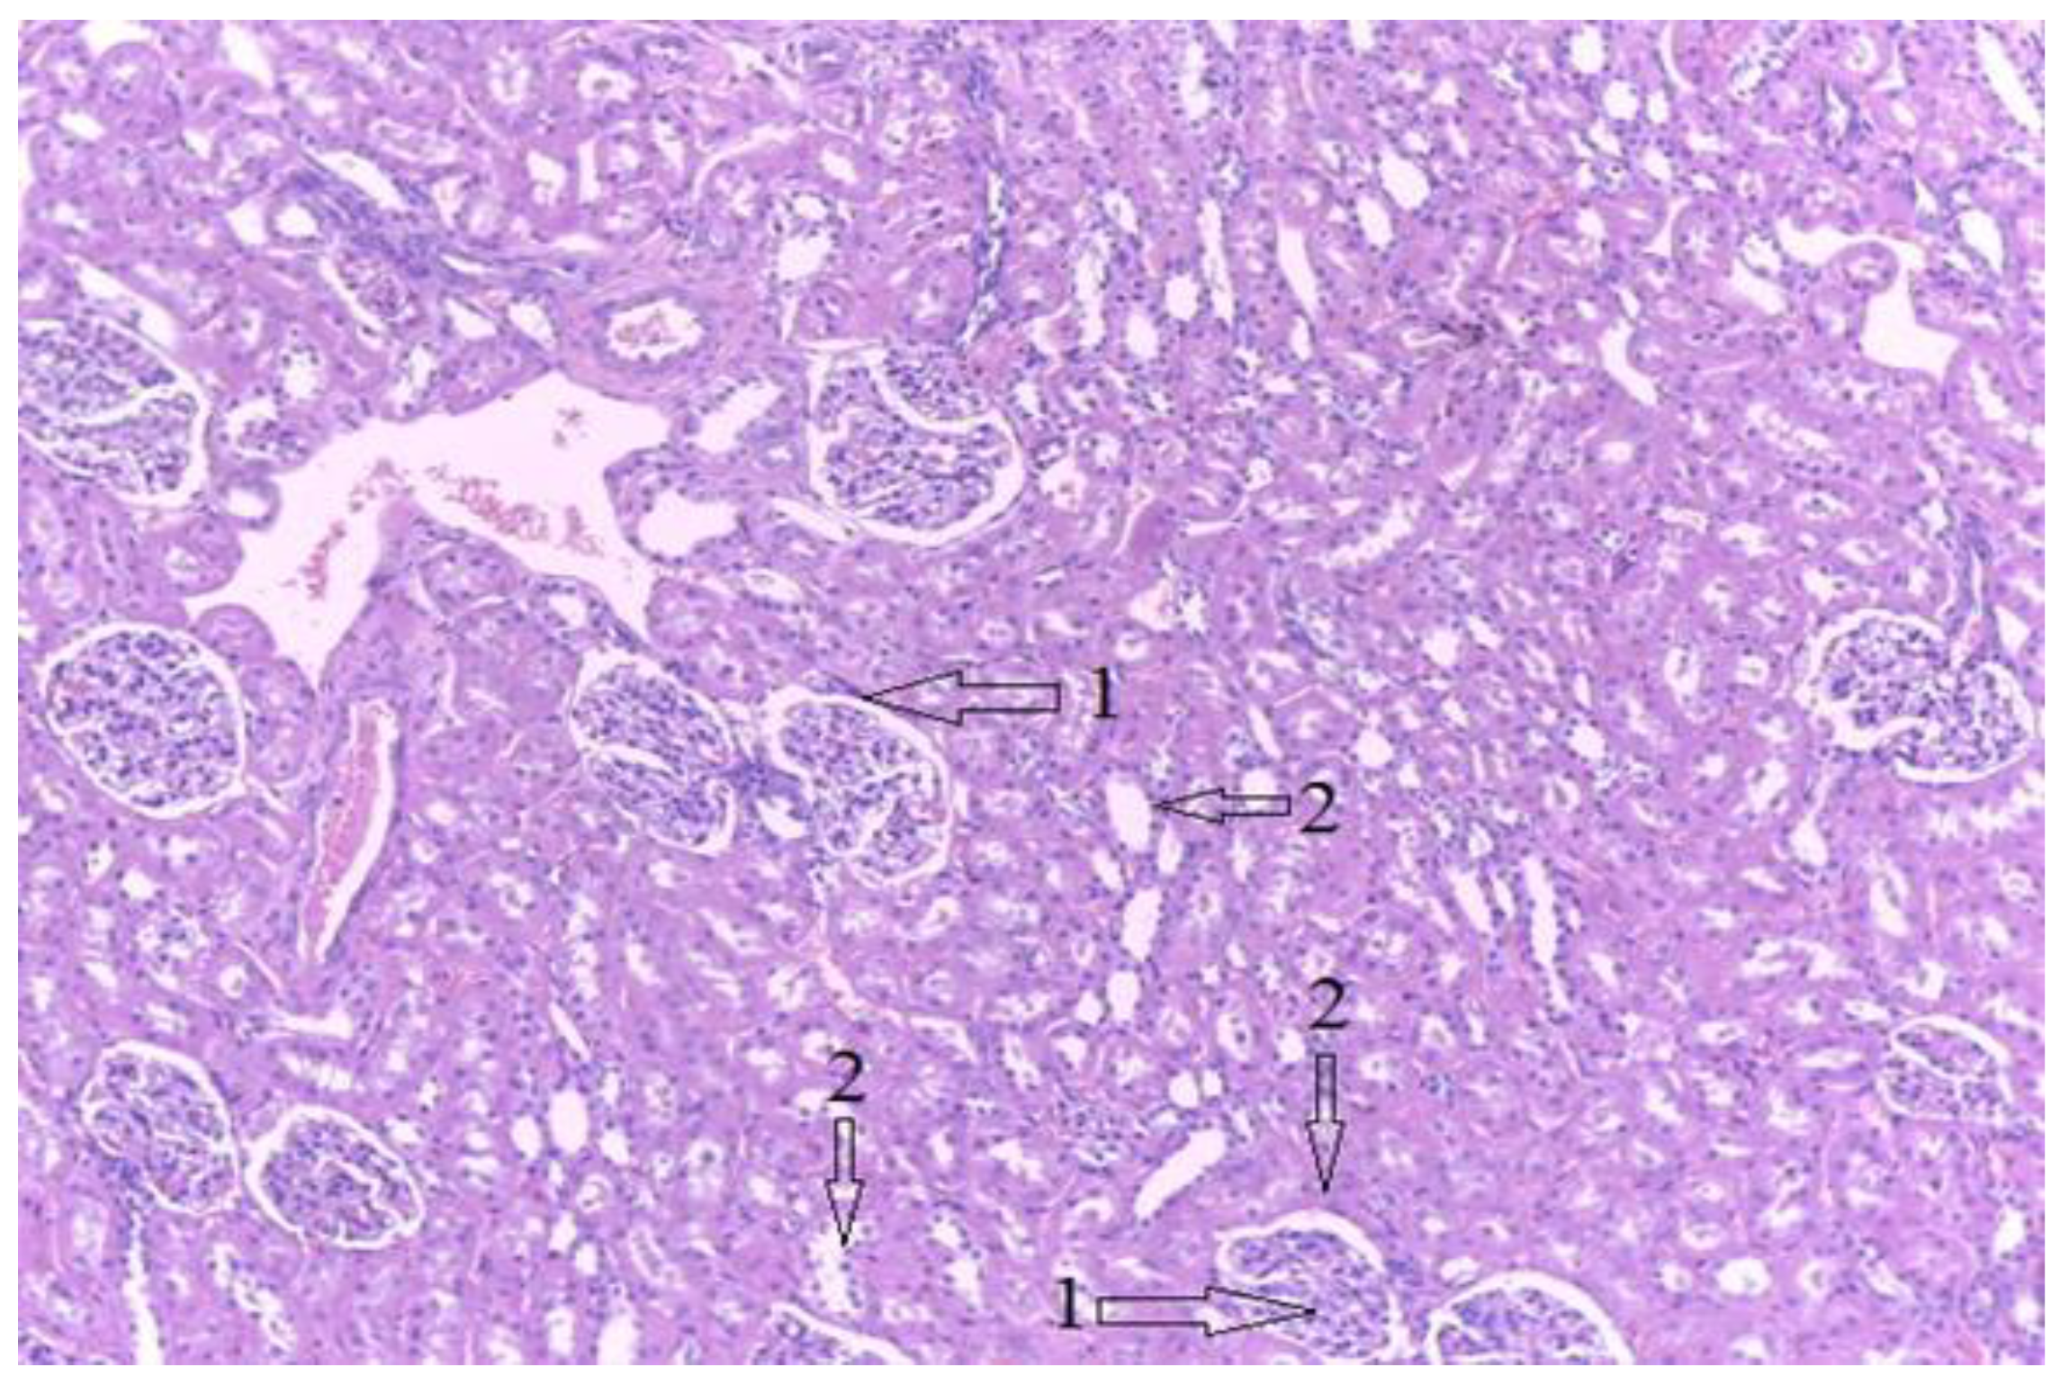

3.3. Histological Results